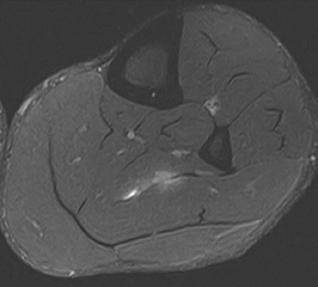

PD STIR - 1024 x 1024 matrix - 3mm slice thickness

Sag T2 - 0.5 x 0.5 min - 0:56 min Ax PD FatSat - 0.6 x 0.6 mm - 1:30 min Cor PD FatSat - 0.6 x 0.6 mm - 1:15 min Cor PD - 0.5 x 0.5 mm - 0:58 min © 2020 CANON MEDICAL SYSTEMS // MREU200040

Fast knee protocol with AiCE on Vantage Orian 1.5T